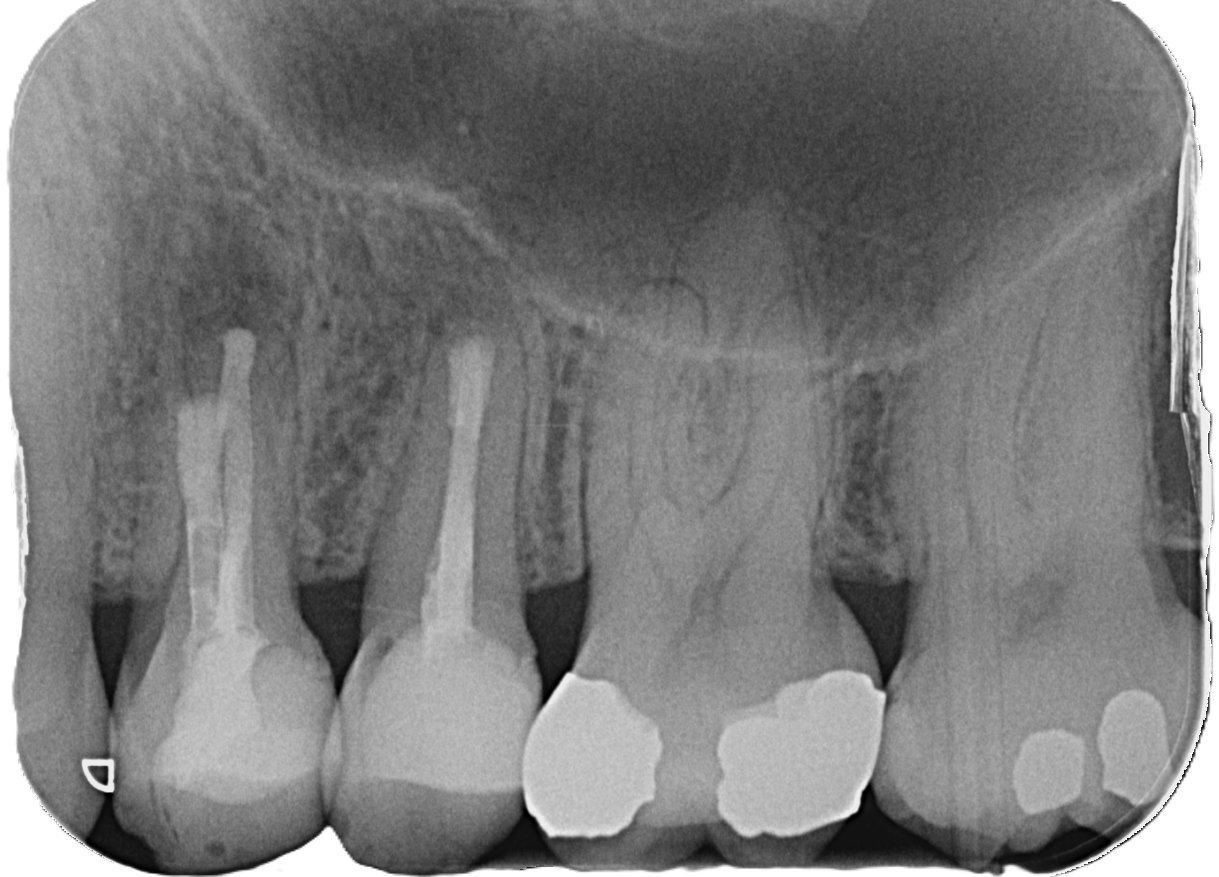

Zahnärztliches Röntgenbild mit mehreren Backenzähnen – Darstellung von Wurzelkanalbehandlungen und Füllungen zur Diagnostik in der Zahnklinik Nordhorn

Vorher

Nachher

Das Ergebnis wird durch Röntgenaufnahmen präzise überprüft: Ein neu gebildeter Knochen im Bereich der Wurzelspitze zeigt an, dass die Kaufunktion vollständig wiederhergestellt ist. Parallel dazu berichten die Patienten über ihre Erfahrungen im Heilungsverlauf und geben Auskunft über die Belastbarkeit des betroffenen Zahnes.